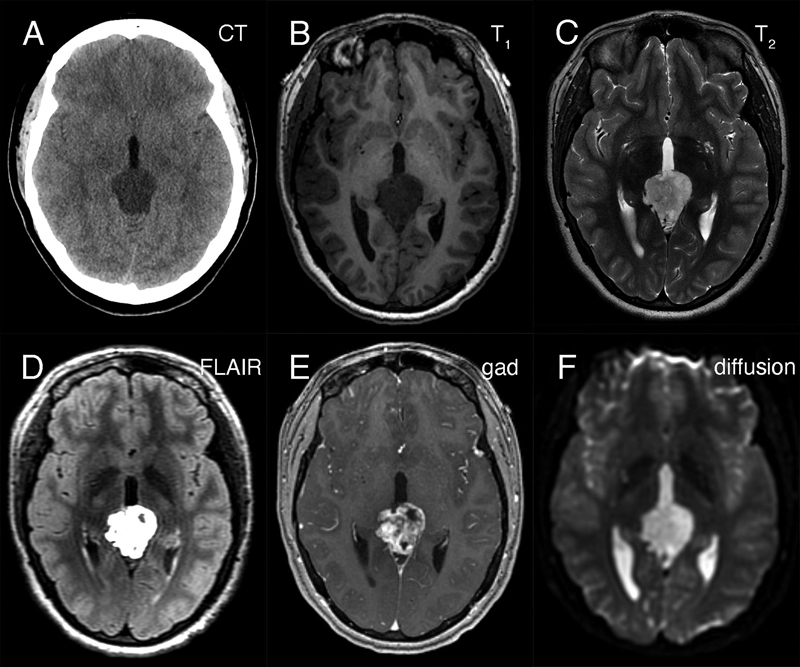

Figure 1: Preoperative neuroimaging. The tumor in the pineal region was hypodense on non-contrast CT head (A), hypointense in T1-weighted (B) and hyperintense in T2-weighted (C) MRI sequences. It was strongly hyperintense in FLAIR sequences (D), showed heterogeneous gadolinium enhancement (E), and did not demonstrate restricted diffusion (F).

Neuroradiology

Two previous reports discussed DMT radiologic features. Unlike the tumour described here, which was hypodense in CT and hypointense in T1-weighted MRI (figure 1A and 1B), the tumor described in Wang, 2021 was hyperdense on CT scans and slightly hyperintense on T1-weighted MRI scans. It is likely that the more prominent desmoplasia illustrated in Wang, 2021, compared to our tumor, correlated with their increased CT signal density. In our patient's tumor, the Alcian blue myxoid component (see figure 5B) was predominant, which correlates with our increased T2 and FLAIR signal (see figure 1C and 1D) and is dissimilar to the isointense T2-weighted signal described in Matsumura, 2021. Similar to the image illustrated in Matsumura, 2021, gadolinium enhancement was heterogeneous in our patient's tumour.